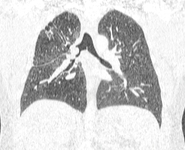

Злокачественная эндобронхиальная обструкция на мультидетекторной КТ: корональная реконструкция, демонстрирующая злокачественную обструкцию правого главного бронха

Из коллекций Хосе Фернандо Сантакруза, дипломированного врача, члена Американской коллегии специалистов в области торакальной медицины, DAABIP, и Эрика Фолка, дипломированного врача, магистра наук; используется с разрешения